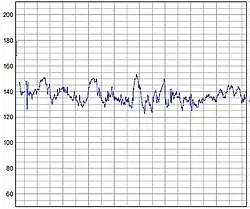

A more precise method of determining heart rate involves the use of an electrocardiograph, or ECG (also abbreviated EKG). An ECG generates a pattern based on electrical activity of the heart, which closely follows heart function. Continuous ECG monitoring is routinely done in many clinical settings, especially in critical care medicine. On the ECG, instantaneous heart rate is calculated using the R wave-to-R wave (RR) interval and multiplying/dividing in order to derive heart rate in heartbeats/min. Multiple methods exist:

- HR = 1000 · 60/(RR interval in milliseconds)

- HR = 60/(RR interval in seconds)

- HR = 300/number of "large" squares between successive R waves.

- HR= 1,500 number of large blocks

Heart rate monitors allow measurements to be taken continuously and can be used during exercise when manual measurement would be difficult or impossible (such as when the hands are being used). Various commercial heart rate monitors are also available. Some monitors, used during sport, consist of a chest strap with electrodes. The signal is transmitted to a wrist receiver for display.

Standard textbooks of physiology and medicine mention that heart rate (HR) is readily calculated from the ECG as follows: HR = 1000*60/RR interval in milliseconds, HR = 60/RR interval in seconds, or HR = 300/number of large squares between successive R waves. In each case, the authors are actually referring to instantaneous HR, which is the number of times the heart would beat if successive RR intervals were constant.